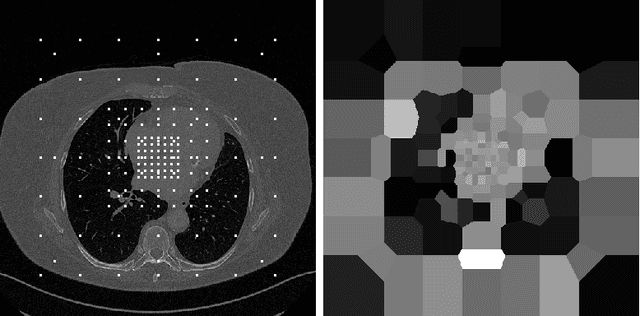

Abstract:Organ segmentation is a fundamental task in medical imaging, and it is useful for many clinical automation pipelines. Typically, the process involves segmenting the entire volume, which can be unnecessary when the points of interest are limited. In those cases, a classifier could be used instead of segmentation. However, there is an inherent trade-off between the context size and the speed of classifiers. To address this issue, we propose a new method that employs a data selection strategy with sparse sampling across a wide field of view without image resampling. This sparse sampling strategy makes it possible to classify voxels into multiple organs in real time without using accelerators. Although our method is an independent classifier, it can generate full segmentation by querying grid locations at any resolution. We have compared our method with existing segmentation techniques, demonstrating its potential for superior runtime in practical applications in medical imaging.

Abstract:We propose a method to match anatomical locations between pairs of medical images in longitudinal comparisons. The matching is made possible by computing a descriptor of the query point in a source image based on a hierarchical sparse sampling of image intensities that encode the location information. Then, a hierarchical search operation finds the corresponding point with the most similar descriptor in the target image. This simple yet powerful strategy reduces the computational time of mapping points to a millisecond scale on a single CPU. Thus, radiologists can compare similar anatomical locations in near real-time without requiring extra architectural costs for precomputing or storing deformation fields from registrations. Our algorithm does not require prior training, resampling, segmentation, or affine transformation steps. We have tested our algorithm on the recently published Deep Lesion Tracking dataset annotations. We observed more accurate matching compared to Deep Lesion Tracker while being 24 times faster than the most precise algorithm reported therein. We also investigated the matching accuracy on CT and MR modalities and compared the proposed algorithm's accuracy against ground truth consolidated from multiple radiologists.